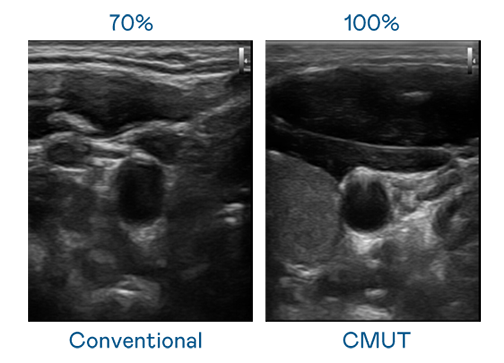

CMUT 技术是一种用电容式微机电元件来产生超音波讯号的技术。与传统 PZT 压电式技术相比,CMUT 频宽增加 30%,更宽频的超音波讯号让影像解析度大幅提升,是实现高影像品质医疗超音波扫描、促进精准医疗发展的关键技术。

超音波影像的解析度高低,首先取决于探头能发出的讯号频宽。澳门威尼斯人 CMUT 可提供高清晰的超音波讯号,提供高频宽、高灵敏度、影像纹理细节更高的超音波影像,协助医护人员缩短影像判读时间及利用精准的医疗影像进行诊断。